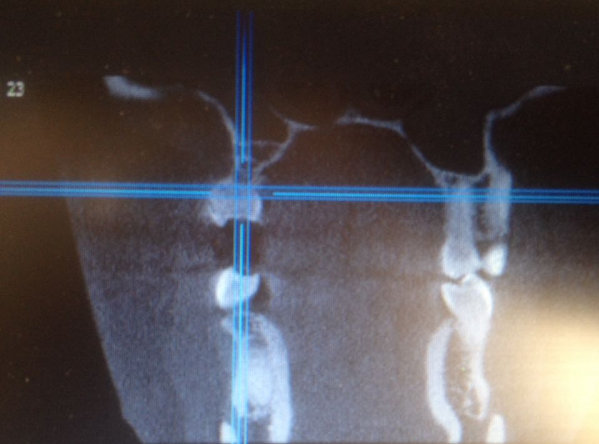

Мне 26 лет, молочные зубы менялись поздно. По личным причинам, когда стал резаться коренной зуб (клык), я не стала вырывать молочный, который был крепким и здоровым. Так на протяжении нескольких лет (очень медленно) прорезался коренной клык и наконец вырос, но на нёбе. Так я ходила с двумя зубками. Никаких неудобств не ощущала. Совсем недавно молочный зуб резко (в течение трёх дней) потемнел.

Помогите, пожалуйста,что нужно делать, удалять оба зуба и ставить мартини? Или после удаления молочного одевать брекеты и ждать пока сдвинется коренной клык?